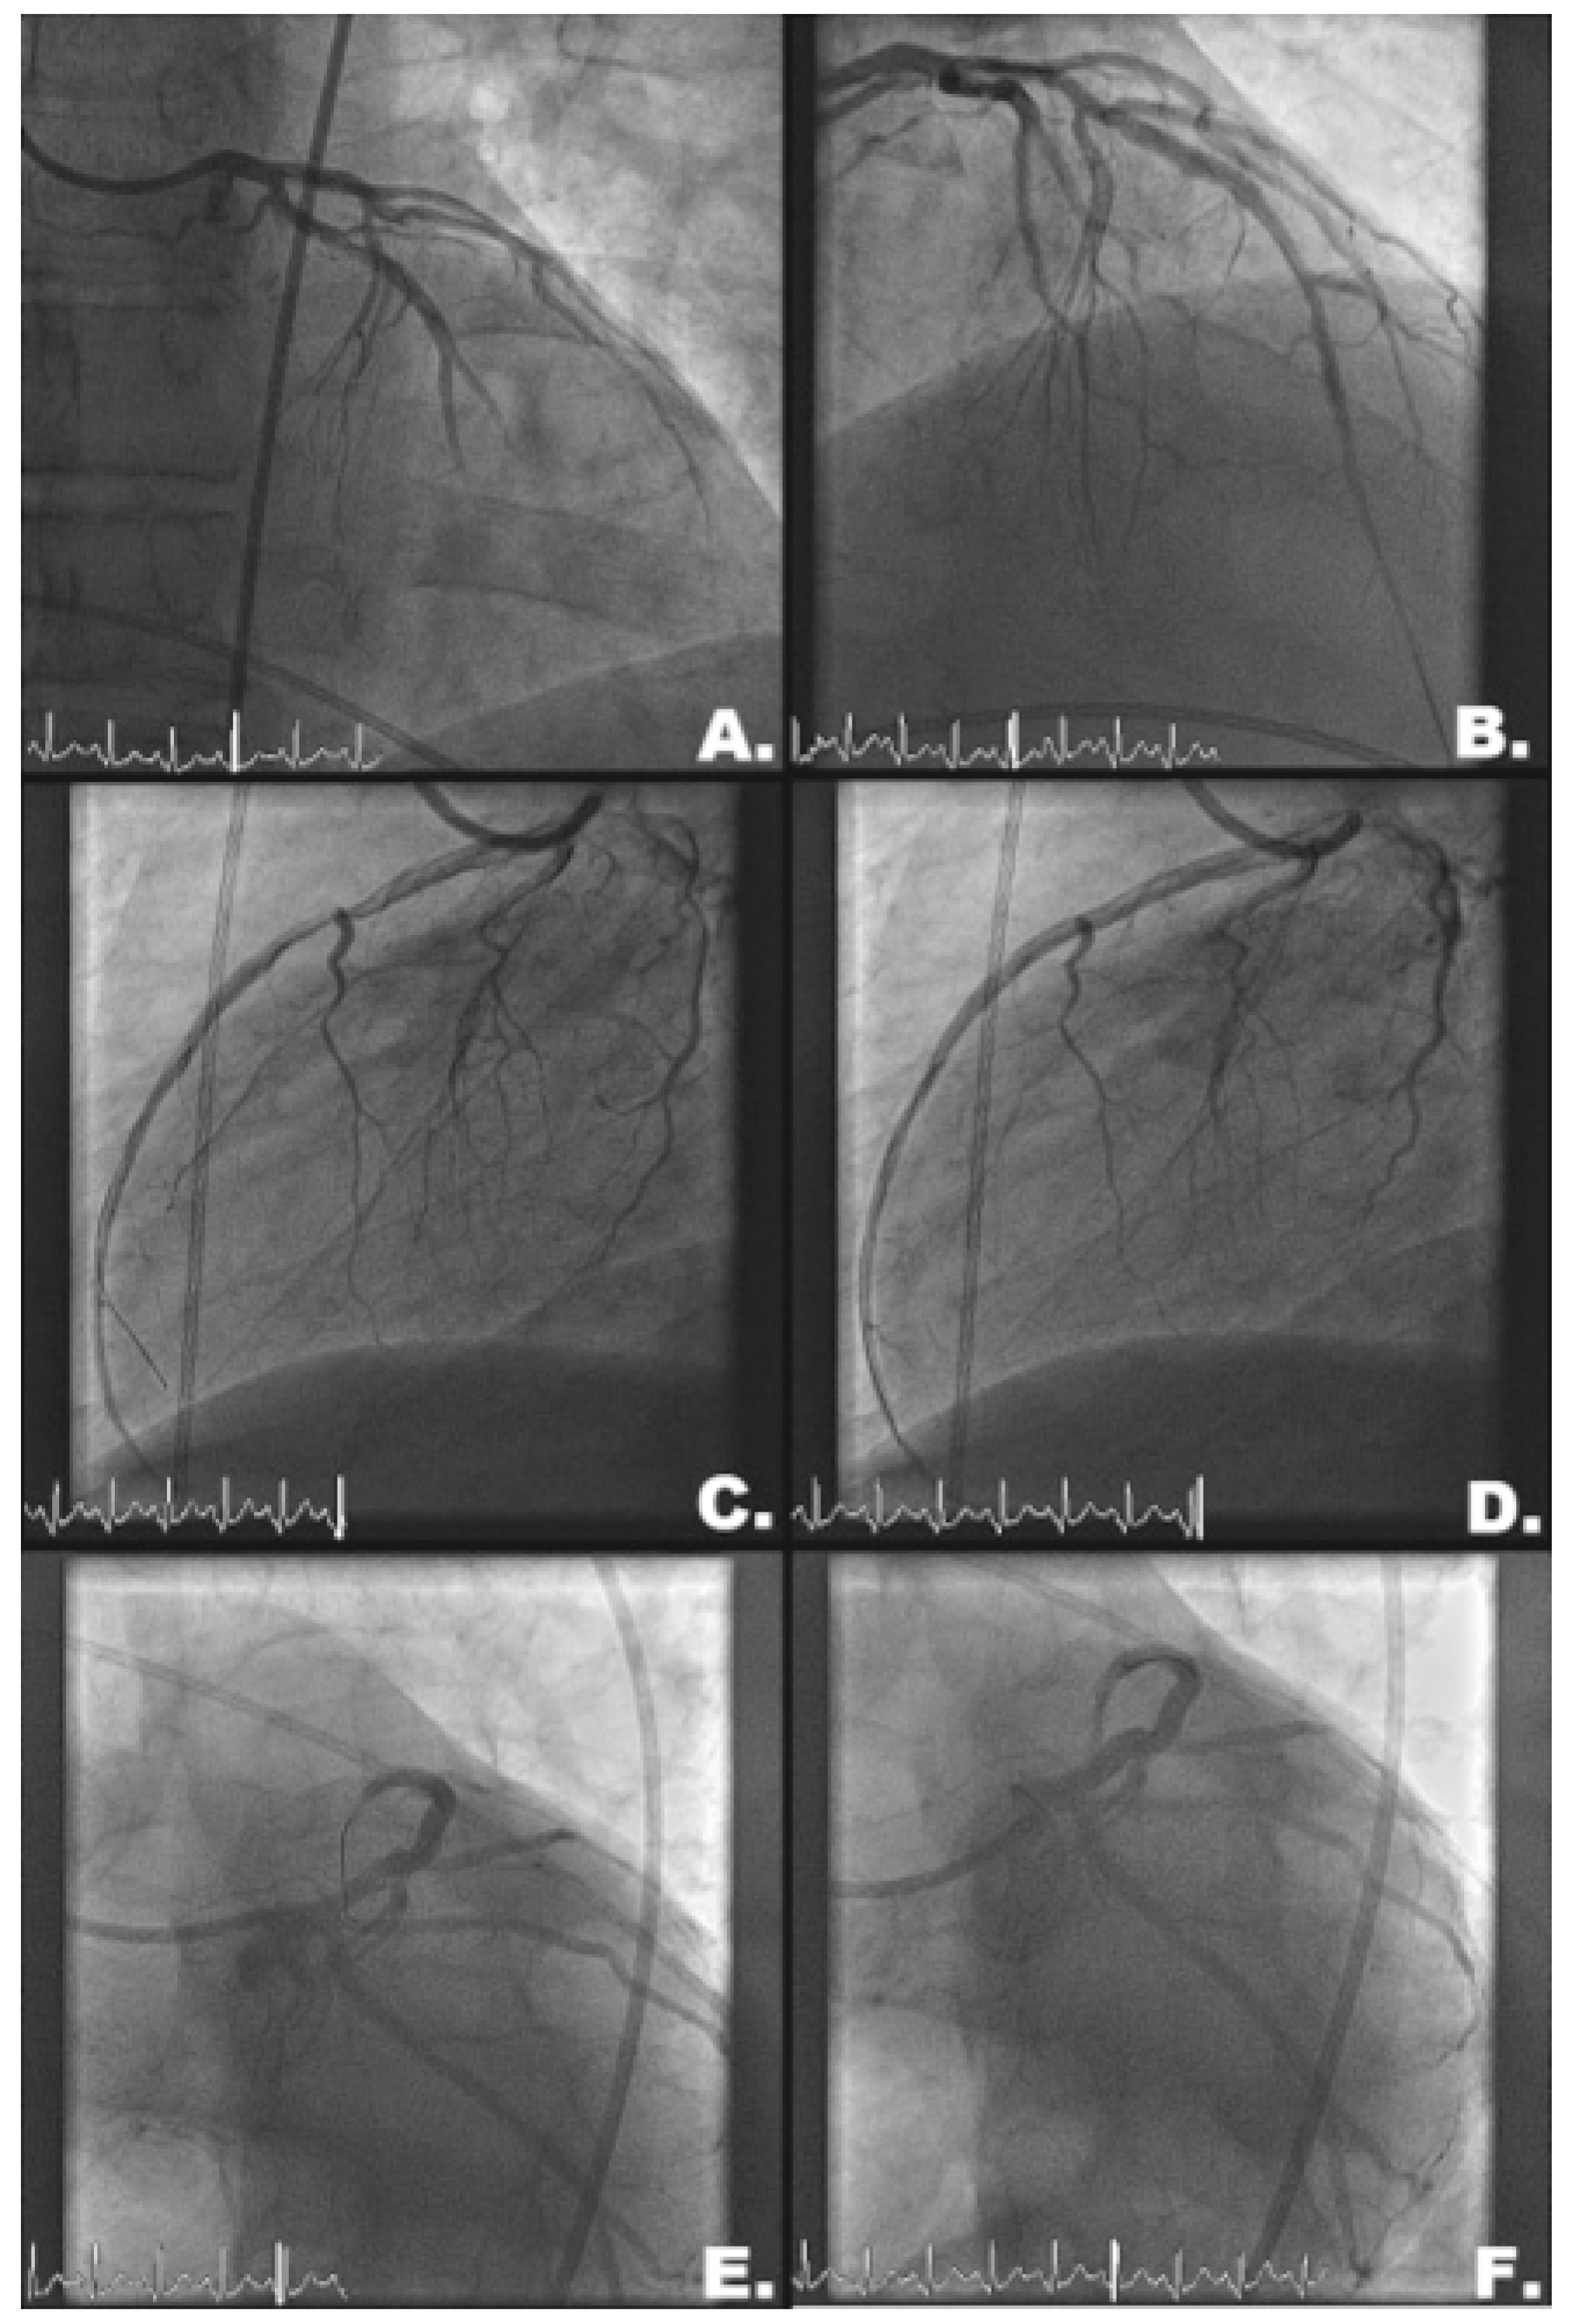

Case description